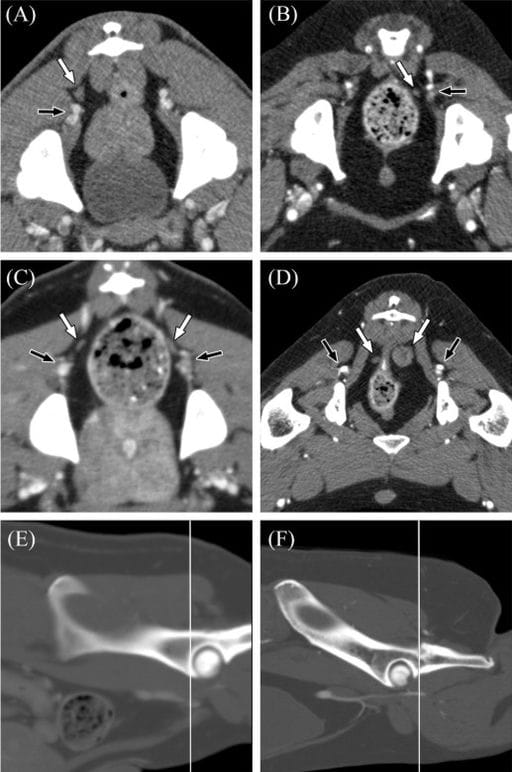

Representative CT images of the positions of sciatic lymph nodes found in dogs. On transverse images, the patient's right is to the left of each image, and transverse images are displayed in a soft tissue window. A, Venous phase postcontrast transverse CT image of a canine pelvis at the level of the mid-acetabula demonstrating a right sciatic lymph node (white arrow) dorsal to the caudal gluteal artery and vein (black arrow). B, Early venous phase postcontrast transverse CT image of a canine pelvis at the level of the cranial to mid-acetabula demonstrating a left sciatic lymph node (white arrow) medial to the caudal gluteal artery and vein (black arrow). Note the poor enhancement of the caudal gluteal vein and other veins on this image due to the relatively early acquisition of the venous phase on this study. C, Venous phase postcontrast transverse CT image of a canine pelvis at the level of the cranial rims of the acetabula demonstrating bilateral sciatic lymph nodes (white arrows) dorsomedial to the respective caudal gluteal arteries and veins (black arrows). D, Venous phase postcontrast transverse CT image of a canine pelvis at the level of the caudal rims of the acetabula demonstrating bilateral sciatic lymph nodes (white arrows) dorsomedial to the respective caudal gluteal arteries and veins (black arrows). Because of the caudal position of these lymph nodes, the coccygeus muscle is seen between the lymph nodes and the respective caudal gluteal vessels. The left sciatic lymph node is the largest one identified in this study (14.9 × 14.5 mm). E, Sagittal reformed bone window CT image of the pelvis of the patient in (C) demonstrating the location of the transverse image (white line). F, Sagittal reformed bone window CT image of the pelvis of the patient in (D) demonstrating the location of the transverse image (white line)

Sciatic lymph nodes were detected in 19 of 121 dogs (15.7%), with bilateral presence in 7 dogs and unilateral presence in 12. A single dog (0.8%) also exhibited bilateral gluteal lymph nodes, coinciding with prior AGASACA metastasis. Sciatic nodes were typically located near the caudal gluteal artery and vein, most often at the level of the cranial or mid-acetabulum. Their median long and short axes were 4.4 mm and 2.6 mm, respectively. Enhancement was mild to moderate in most nodes. While some nodes appeared normal, others were enlarged or heterogeneous, particularly in dogs with metastatic disease. Over half of affected dogs had concurrent lymphadenopathy elsewhere.